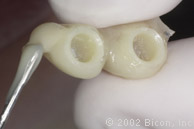

Установка двух 5.0mm x 4.0mm Stealth Shouldered Abutment

Stealth One-Piece Acrylic Sleeves

Изготовление временной конструкции по шаблону

Использование самотвердеющей пластмассы для изготовления временной конструкции